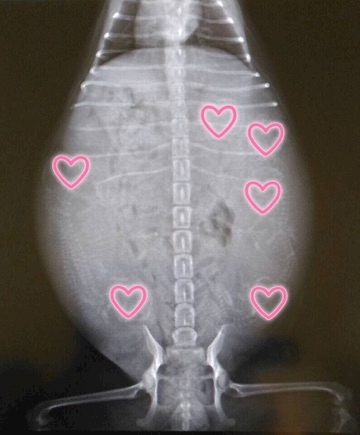

4匹の命が

宿ってるはずが……

6匹います

レントゲン

が頭だよぉ~~

チワワにしては

6匹は多いらしく

難産になり母体も

危険という事で

帝王切開予定……